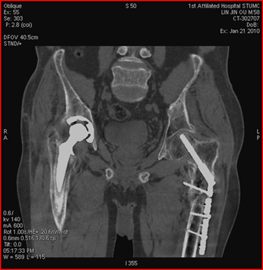

常規(guī)CT 寶石能譜CT

140keV能量成像可以除去金屬引起的偽影,更加清晰觀察術(shù)后情況